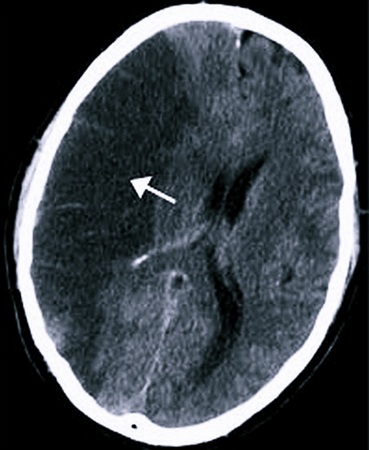

Есть симптомы, которые точно свидетельствуют о том, что у больного случился один из двух типов инсульта:

- Геморрагический. Происходит кровоизлияние в ткани мозга.

- Ишемический. Образуется некроз отдельного участка мозга.

Чтобы обнаружить подобные симптомы, нужно провести диагностику при помощи МРТ, КТ, ЭЭГ. Нельзя доверяться только субъективным ощущениям.